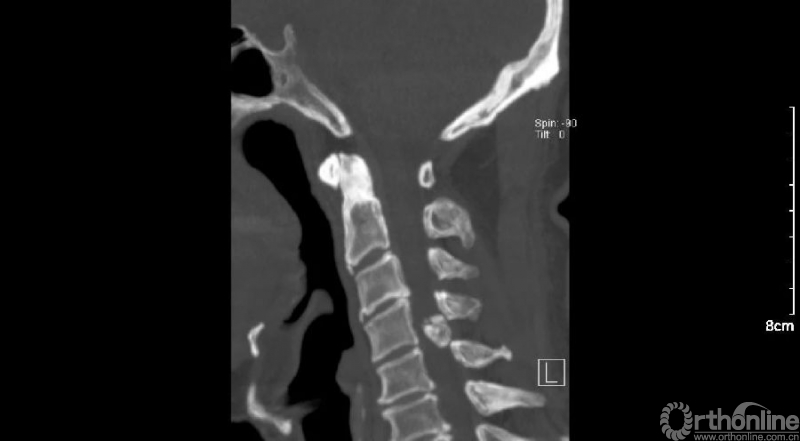

入院查体患者四肢肌张力高,双侧hoffman阳性。CT及MRI检查提示C4/5左侧关节突内缘有一巨大骨块(15mm*16mm),相应节段椎管严重狭窄。椎管内骨块的前端还有一游离骨块。

影像学资料